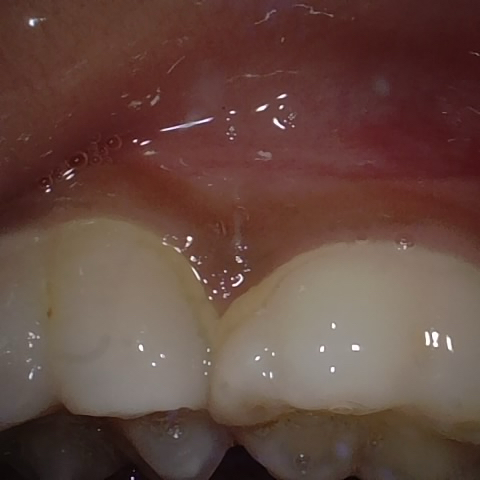

Incorrect Quality Level

The reference annotation for this image is

None

.

Please select the correct quality level.

Image 345 / 1715

Annotated as "Good"